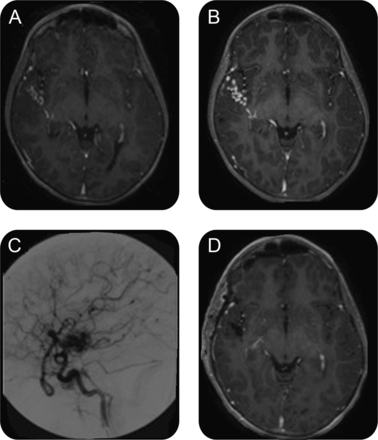

一个5岁的男孩动手术nonmetastatic第四脑室的成神经管细胞瘤(图1)。化疗和bifractionated craniospinal放射治疗管理。四年后,t1加权磁共振成像对比异常血管在右大脑侧裂透露,在随访期间逐渐增加;血管造影证实的动静脉畸形(AVM) (图2)。即使它是无症状的,其位置和增长促使我们治疗(栓塞然后残留病灶的切除)。这非常罕见的情况下辐射诱导AVM表明,当异常血管成像发生在后续1,2与血管造影进一步调查是必要的,考虑进一步治疗。